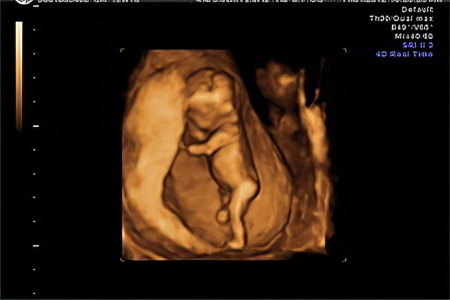

УЗИ

Данное исследование предназначено для женщин на сроке 11-14 недель беременности, состоящих на учёте в женской консультации. Оно позволяет уточнить срок беременности и предполагаемую дату родов, а также оценить развитие ключевых внутренних органов и выявить возможные патологии.

Квалифицированный специалист сможет легко определить пропорции бедренных и других длинных костей, форму рук и ног, а также изучить структуры сердца, печени, пищеварительной и выделительной систем, а также мозга.